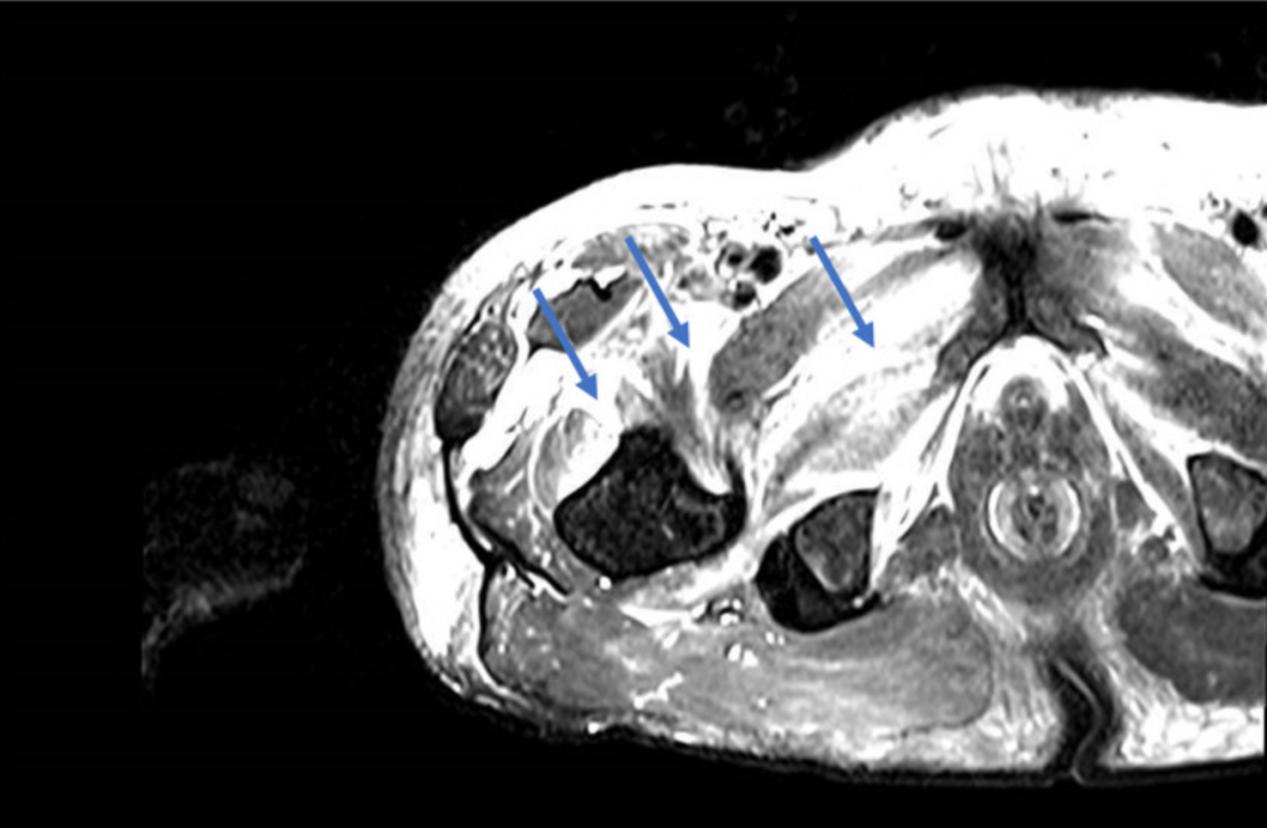

假定诊断为脓性肌炎,患者接受静脉注射抗生素治疗,但无改善。广泛的实验室检查提示病毒、细菌和寄生虫呈阴性。排除自身免疫和毒物。然后考虑糖尿病性肌肉梗死。受影响大腿的磁共振成像(MRI)显示与筋膜周围和肌肉周围水肿相关的内收肌、股肌和缝匠肌的体积和异质性增加,以及与肌肉梗死相关的多个对比度增加区域(图2)。肌肉活检显示炎性浸润和骨骼肌坏死区域(图3)。

图2